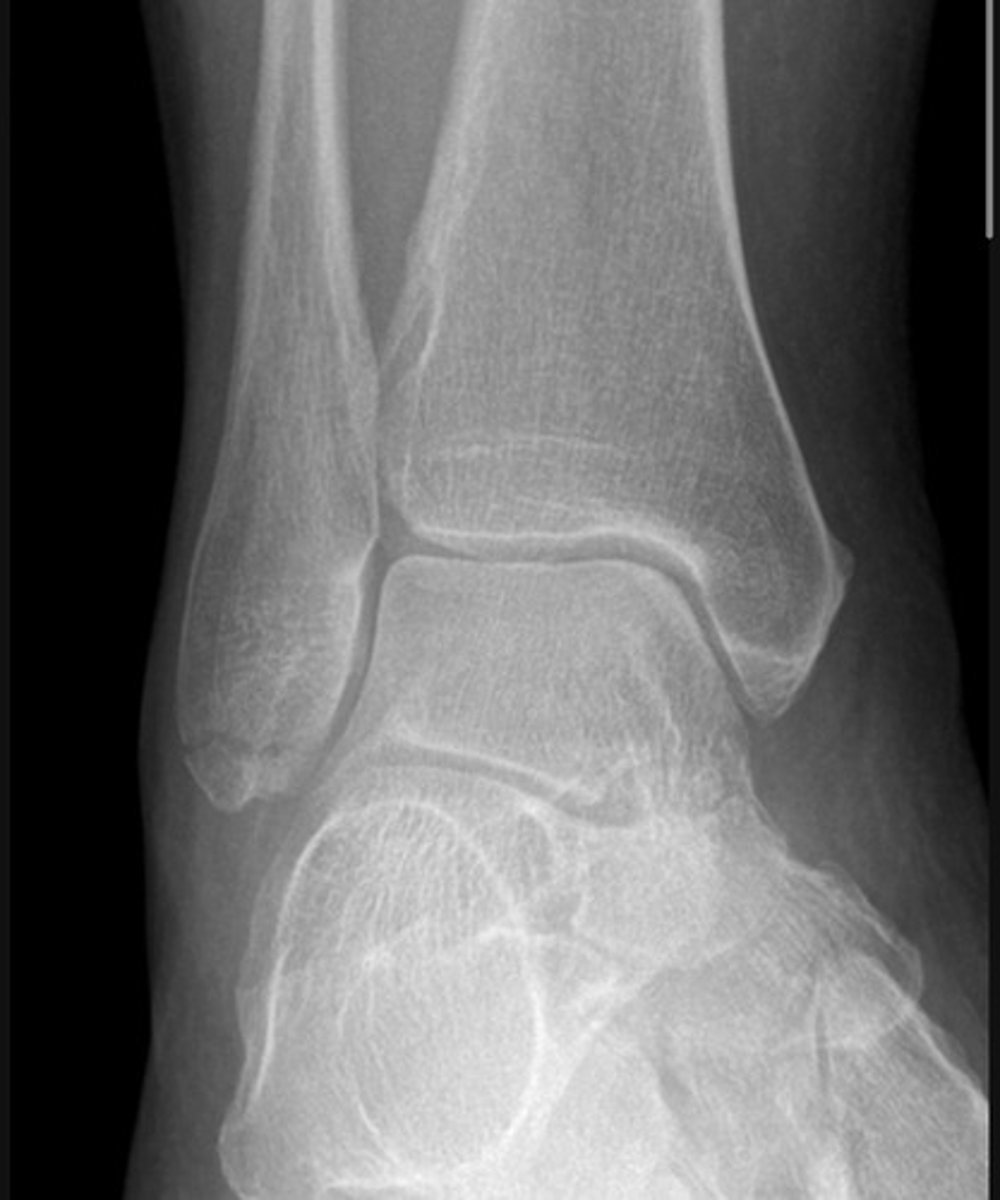

Weber A fracture of the fibula/ lateral malleolus

Weber B feature of the fibula/ lateral malleolus

Bimalleolar fracture.